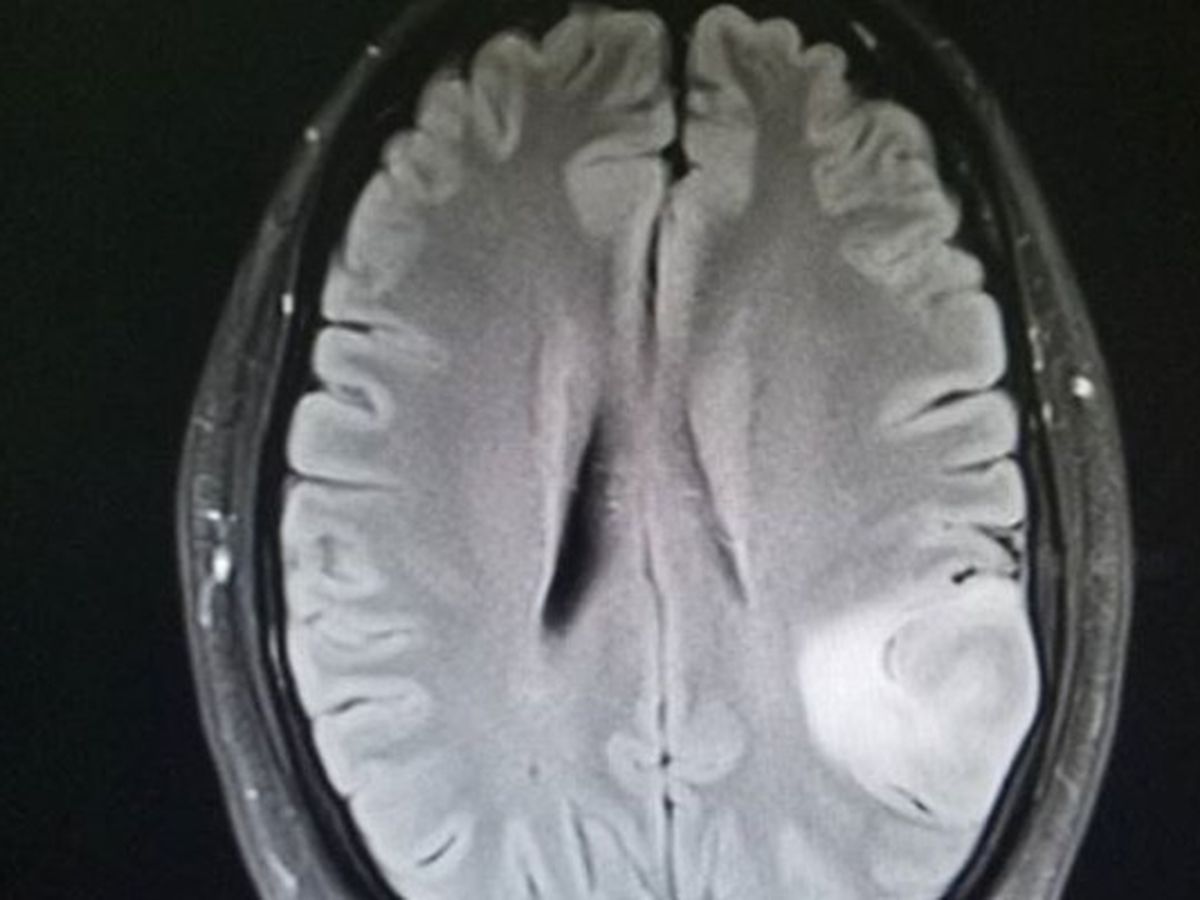

On 7/17/2017, my husband starting have trouble speaking.  We never knew what journey was ahead of us. On 7/19/2017 he had a brain tumor removed which was 4x4x3. The doctors are guessing its grade 3 at the moment, but we are awaiting 2nd biopsy results from UVA. We are expecting lots of bills from the hospital, in which David cannot work right now to pay. The amount I chose is how much his out of pocket is, I know it's highly unlikely but I dont want him stressing over bills. I'll keep everyone  updated as we find out more.